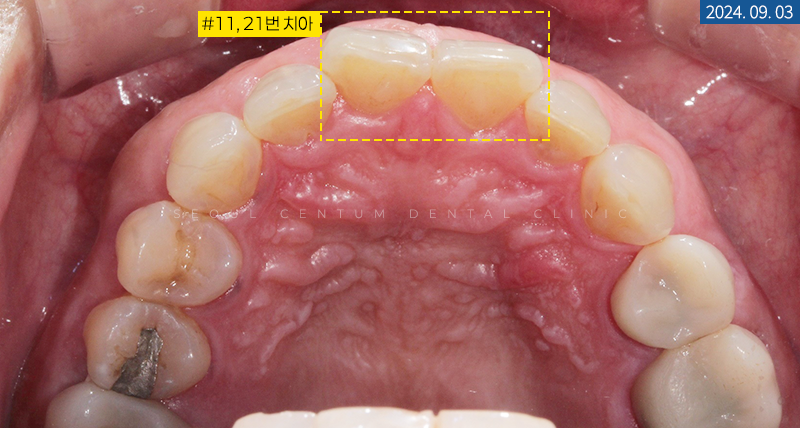

환자분께서 치아 형태와

색조를 변경하기를 원하시는

#13~23번 치아 중 대부분은

치질을 0.1mm가량 삭제하는

무삭제라미네이트가 가능하지만

#11, #21번 치아는 Rotation이 심한 것으로 확인되어

0.3~0.5mm의 평활면을 절삭할 수 있다고

충분히 설명해 드린 후 술식을 진행하게 되었습니다.